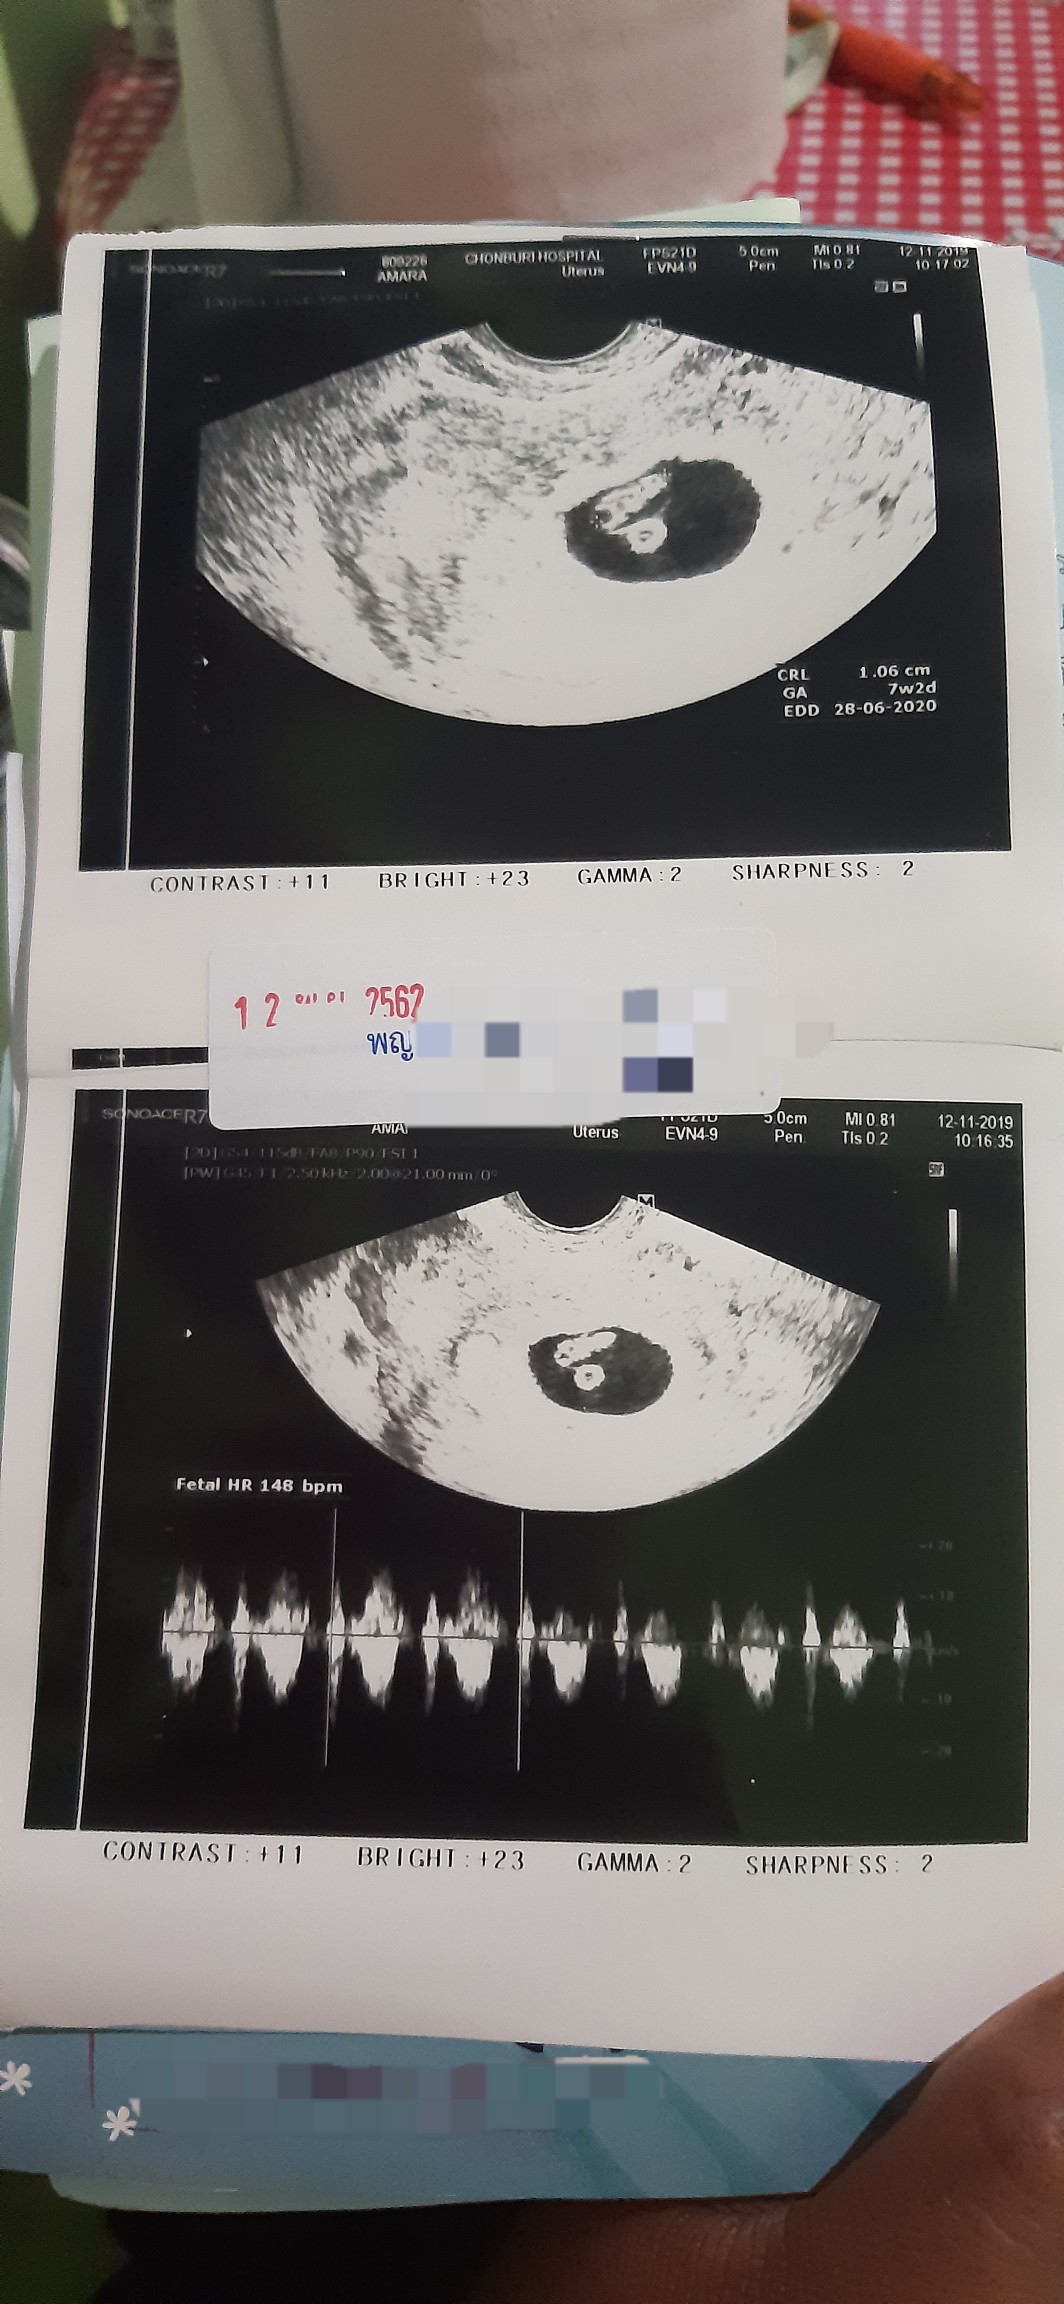

7w+ค่ะ เจ้าจิ๋ว